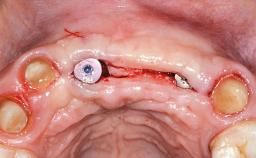

Replacement of Four Incisors with a Fixed Partial Denture on Two Narrow-Neck Implants after Implant Failure

| Type of Implants | One-Piece|Reduced-Diameter |

| Bone Augmentation | Horizontal|Staged|Vertical |

| Augmentation Materials | Autogenous block(s)|Xenogenous|Membrane |

| Bone Volume | Deficient vertically or deficient vertically AND horizontally |